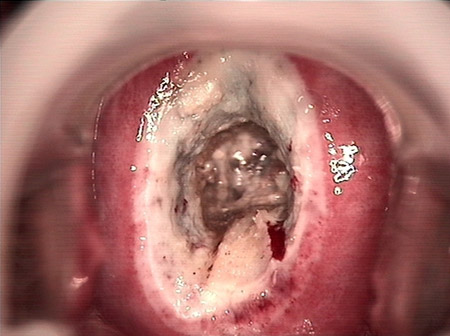

婦科leep錐切手術(shù) CIN2-3

CIN 2-3

CIN 2-3 碘著色后

CIN 2-3 leep術(shù)后

CIN 2-3 修復(fù)后

CIN 2-3 修復(fù)后(圖2)